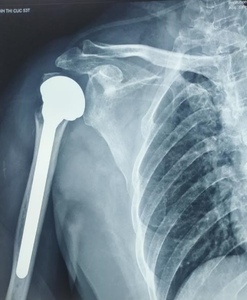

Image Illustration of Clinical Cases in the Study

Postoperative X-ray showed a normal axis in 94% of total cases.